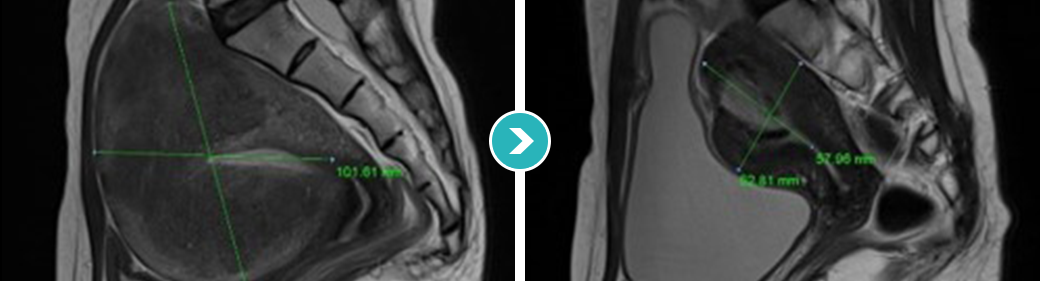

심한 생리통과 항문통증으로 자궁선근증이 진단되어 자궁선근증 하이푸 치료를 위해 입원하셨습니다.

하이푸 시술전 MRI사진상 자궁은 6.5크기로 커져서 자궁후벽을 중심으로 자궁선근증성 변화가 관찰됩니다.

아래의 MRI 사진은 자궁선근증 하이푸 시술 전후의 사진을 비교한 사진입니다. 자궁선근증 하이푸 치료후 90%이상 치료되어 치료부위가 회색과 검은색으로

나타나며, 차후에 좋은 경과를 기대하며 가장자리의 잔여병변은 호르몬 치료하면서 경과관찰 하시도록 하였습니다.